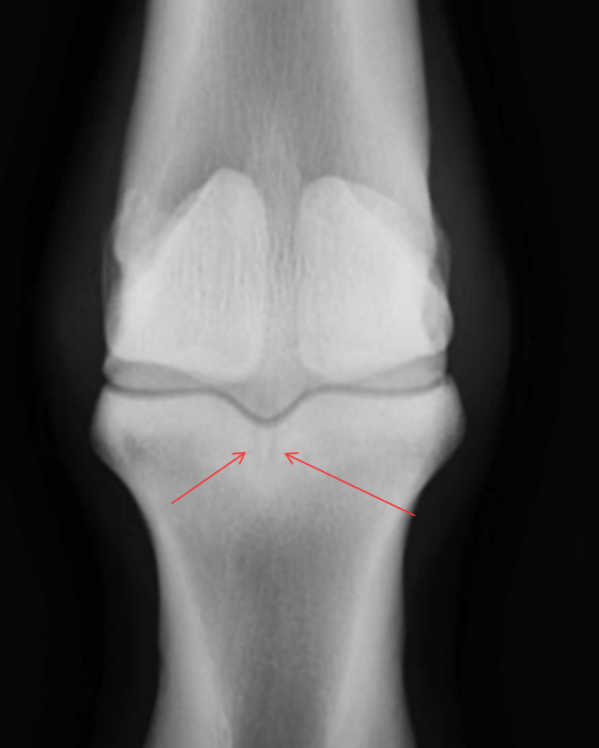

Fractuur van welke structuur?

Fractuur van de laterale condyl van de humerus

Intra- of extra-articulair?

Intra-articulair in het radio-ulnaire gewricht

Configuratie?

Partiële fractuur

We zien 2 breuklijnen maar het is 1 fractuur! De opname is niet loodrecht op de breuk